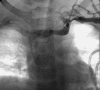

Central venous access is increasingly becoming the domain of the radiologist, both in terms of the insertion of central venous catheters (CVCs) and in the subsequent management of these lines. This article seeks to provide an overview of the CVC types available for paediatric patients and a more detailed explanation of the spectrum of complications that may lead to catheter malfunction. A standard catheter contrast study or 'linogram' technique is described. The normal appearances of such a study and a detailed pictorial review of abnormal catheter studies are provided, together with a brief overview of how information from catheter investigations can guide the management of catheter complications.